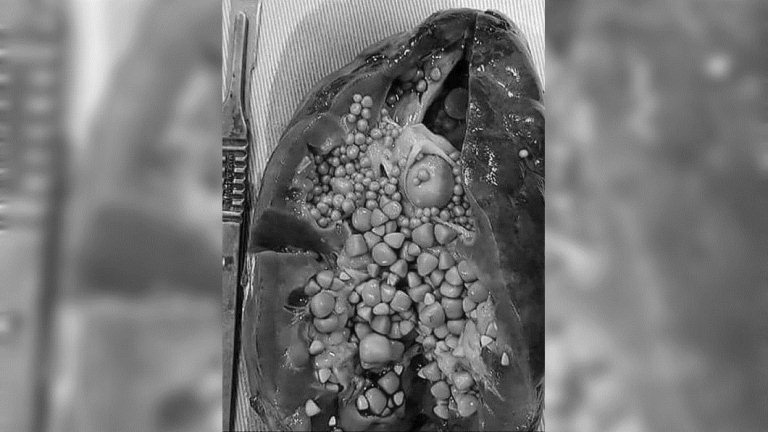

(圖翻攝自臉書)這張腎臟塞滿了大大小小、六十幾顆結石的照片在網路上瘋傳,醫師看了都說「這顆腎臟已經不行了,必須摘除!」